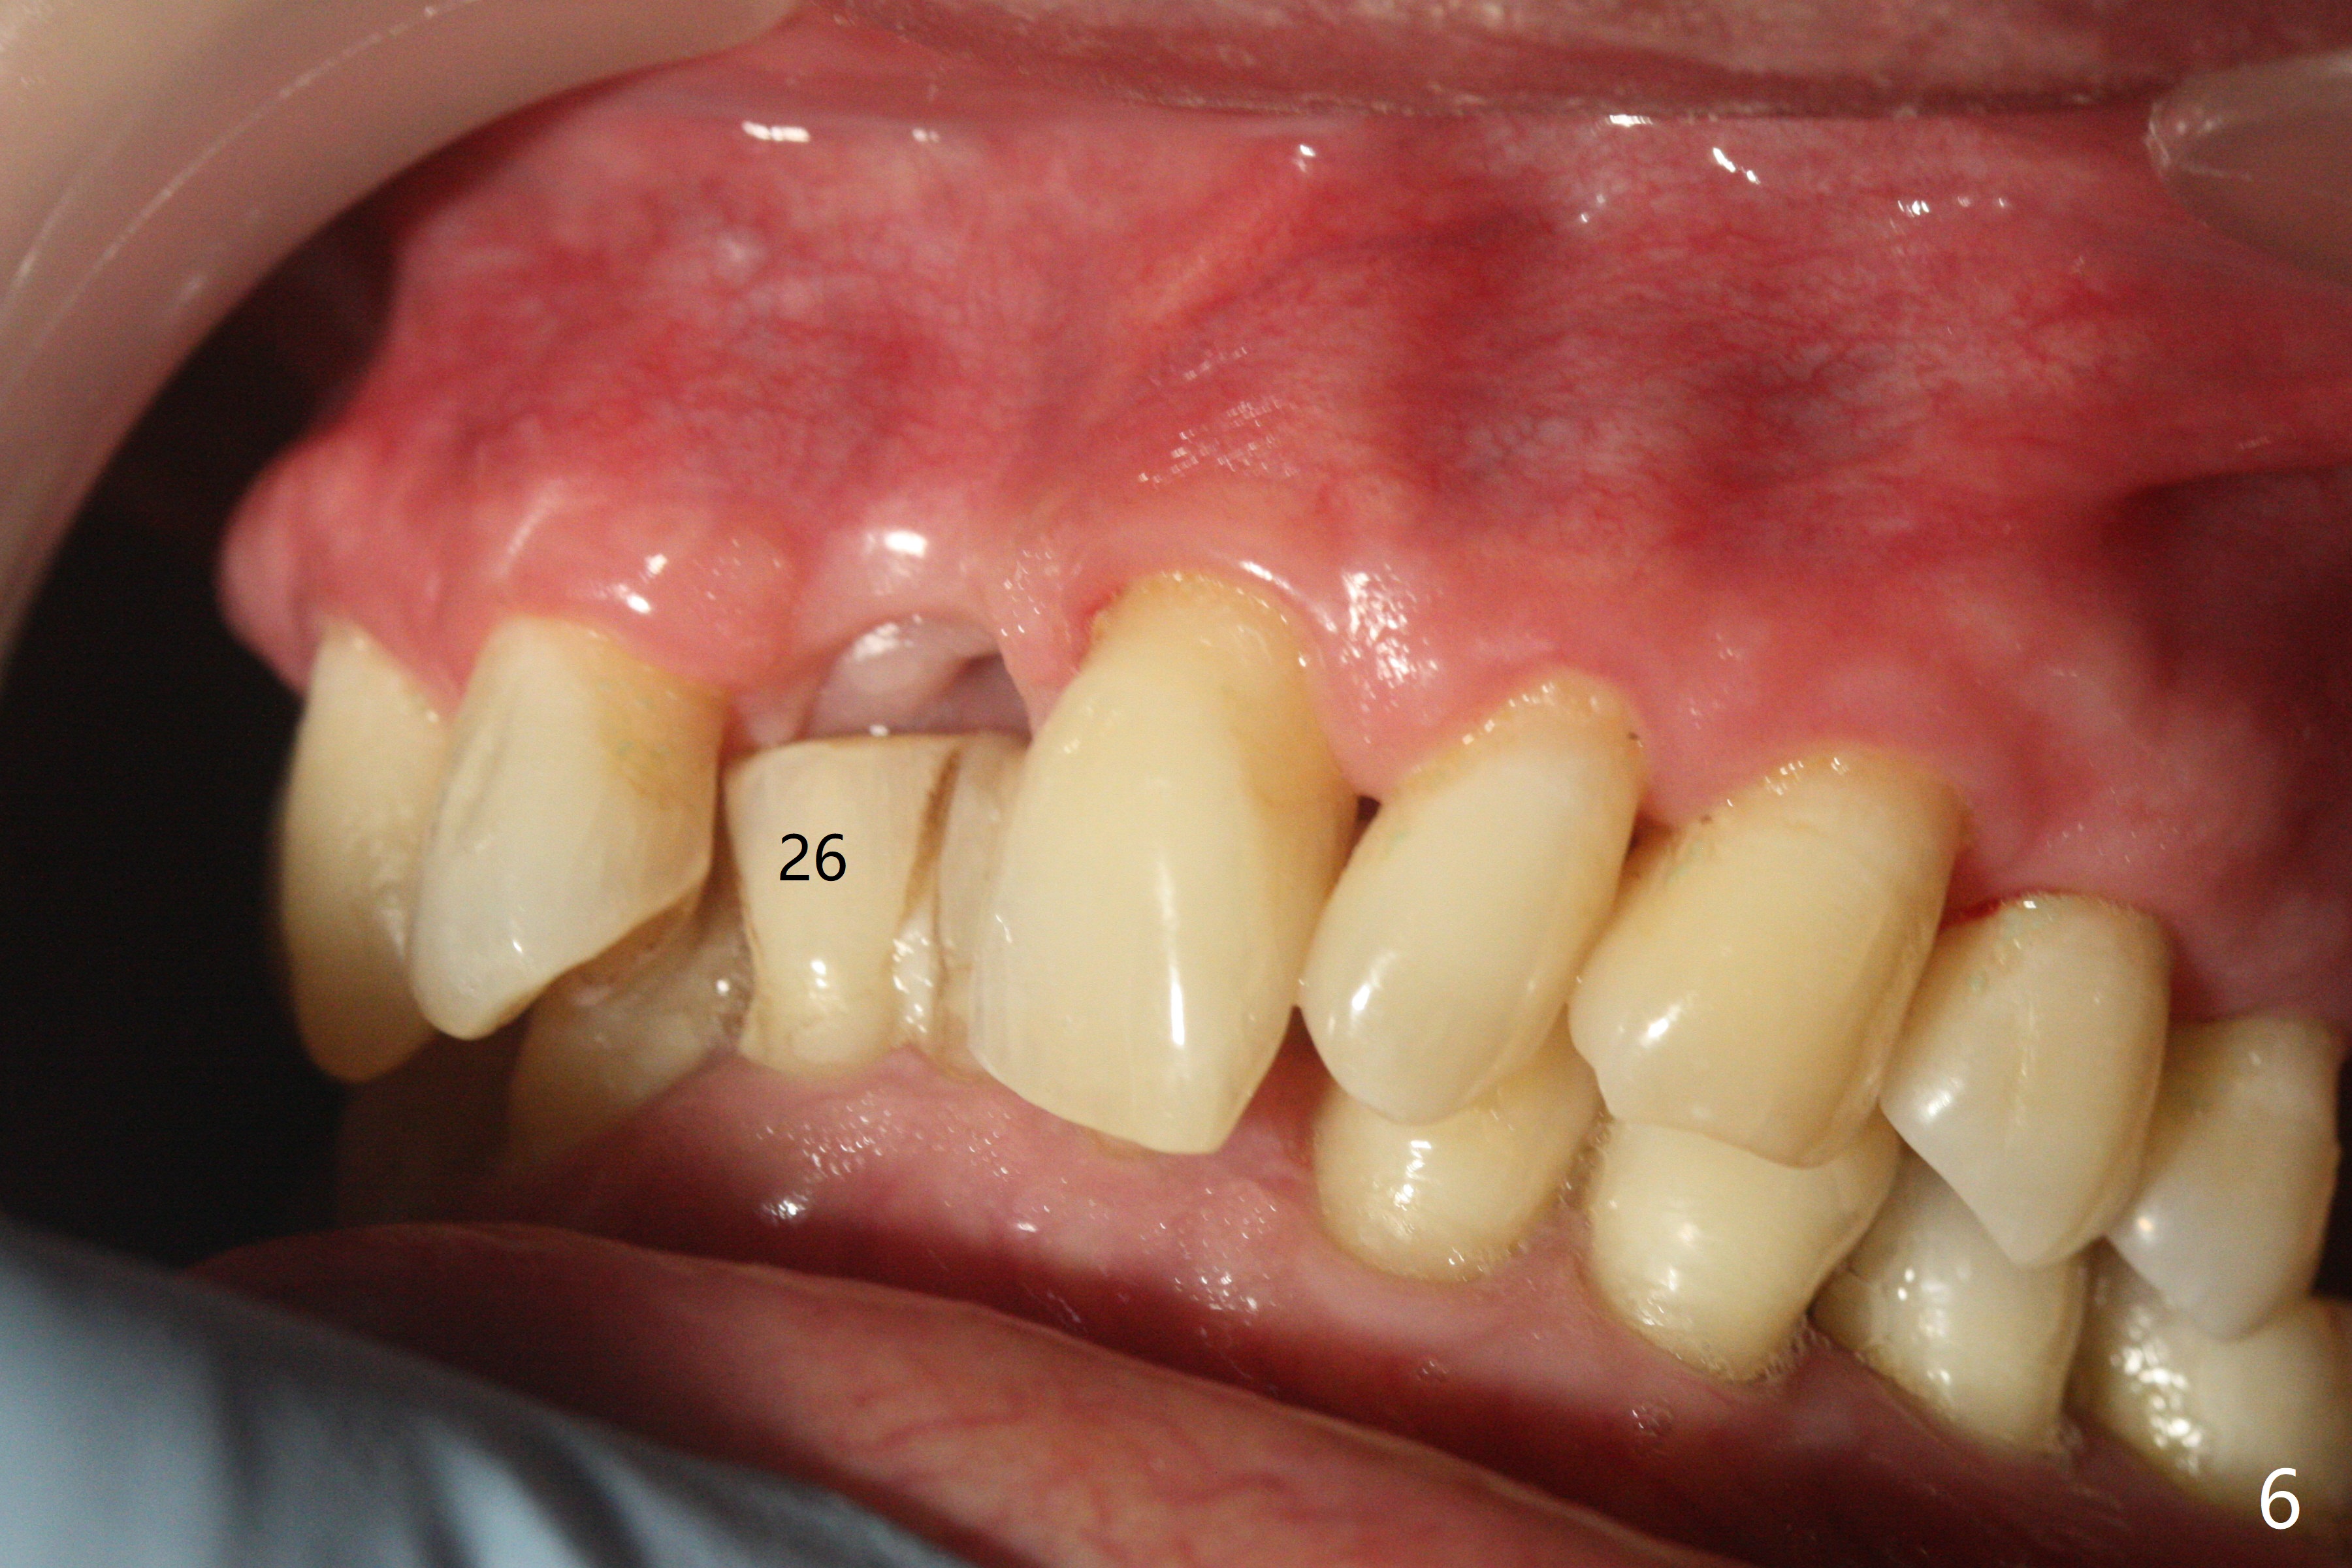

A 69-year-old man (ex-soldier) had the tooth #8 extracted for a flipper nearly 8 years earlier (Fig.1 (obliterated canal)). A denture tooth is added at #14 after extraction in NY a few years later (Fig.2). In spite of sufficient bone width at #8, a 2.5x10 mm mini implant will be chosen to reduce the chance of palatal thread exposure (Fig.3 P). A 5x8.5 mm implant will be placed at #14 to achieve enough stability and not cause sinus complication (Fig.4). Take preop photos to show the anterior deep overbite and overjet. In fact the patient canceled the surgery. Two years later, he returns with history of right TMJ dislocation, which may be related to reduced mastication efficiency and partial edentulism (Fig.5,6).